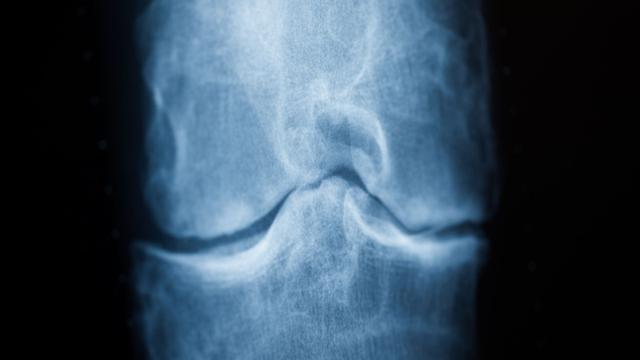

V Nemčiji se krepijo prizadevanja za izboljšanje in pospešitev diagnosticiranja ter zdravljenja revmatičnih bolezni. Namen teh ukrepov v deželi Rheinland-Pfalz je zgodnje odkrivanje revme, kar naj bi pripomoglo k preprečevanju nadaljnjih zdravstvenih težav in optimizaciji terapevtskih postopkov. Iniciativa poudarja pomembnost zgodnje intervencije pri revmatičnih obolenjih.